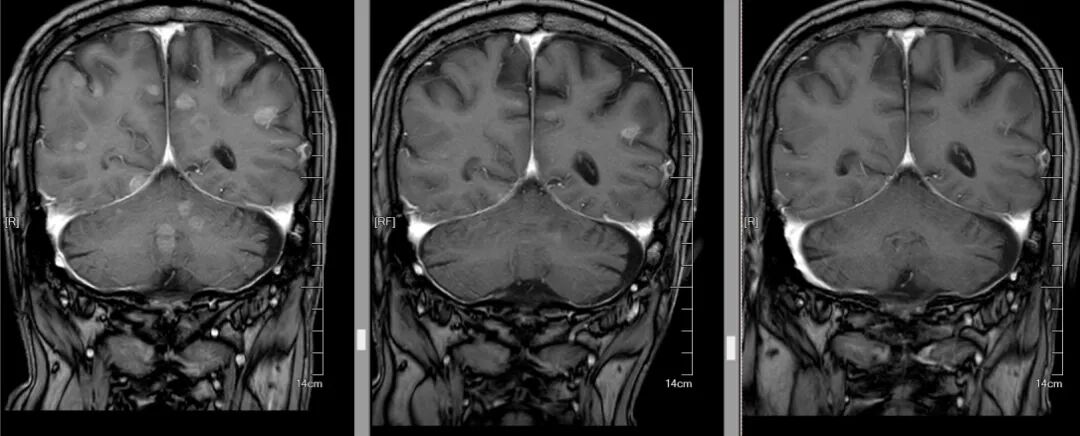

在第二周期治疗前的复查中,当肿瘤科将最新的胸部CT和头颅MRI图像调出来时,结果让人振奋:双肺原本密密麻麻的粟粒样转移结节,大多缩小至模糊不清,肺部原发灶也小了很多;双侧胸膜增厚明显变薄,原本被肿瘤侵犯的纵隔淋巴结也显著缩小;最令人惊喜的是头颅MRI,之前的十余处脑转移灶消失,近乎达到了肿瘤治疗中极具含金量的完全缓解(CR)标准!

△从左至右,颅内肿瘤逐渐减少